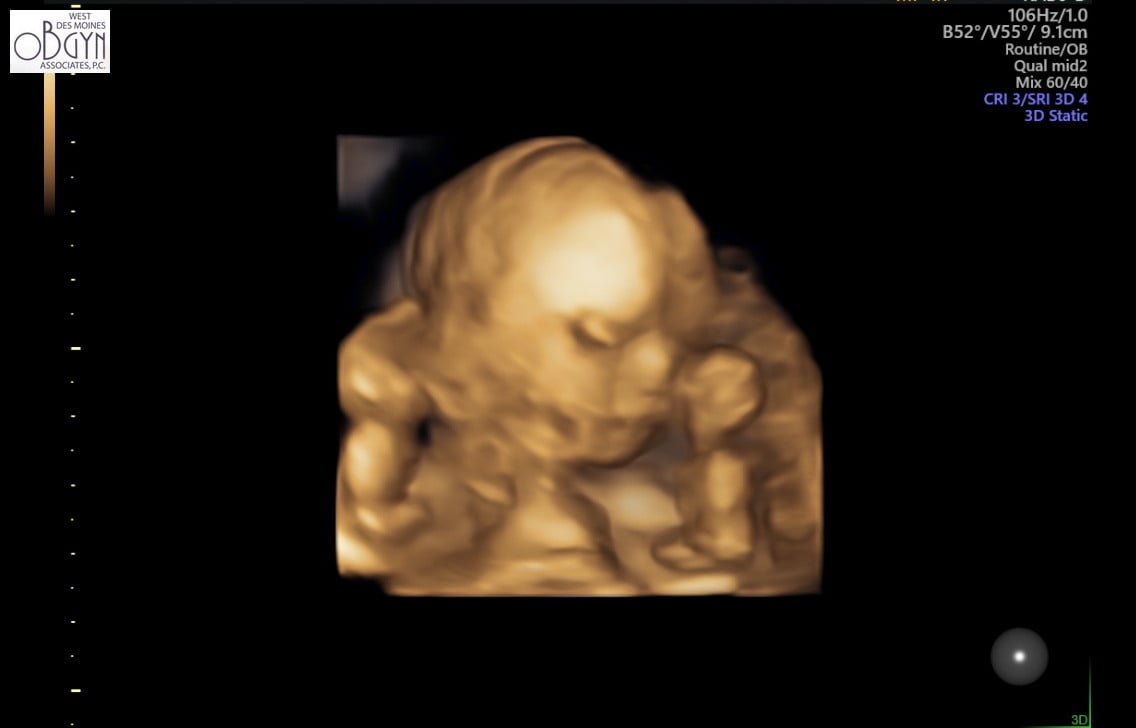

finally a freaking ultrasound! had my NT scan yesterday at 11 weeks 6 days! now just waiting for my Panorama results!